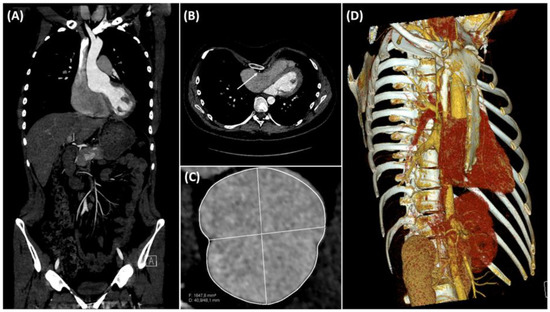

2. Case Description

| Case report | 18 | M | 4.5 | Longitudinal midline | Midsternotomy | Aorta and right atrium | Bentall | Modified Ravitch | Pericardial and pleural effusion | 56 | 44 | 270 | 370 |